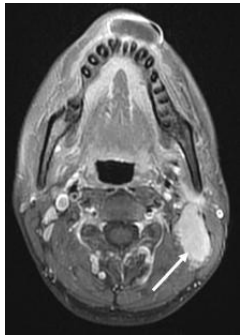

77 (A)聽神經瘤(acoustic neurinoma) (B)顏面神經瘤(facial neurinoma) (C)中耳膽脂瘤(cholesteatoma) (D)鼻咽癌(nasopharyngeal carcinoma)

78. 承上題之病人,下圖白色箭號所指的最可能為何?

(A)聽神經瘤(acoustic neurinoma) (B)顏面神經瘤(facial neurinoma) (C)中耳膽脂瘤(cholesteatoma) (D)淋巴結轉移(metastatic lymphadenopathy)